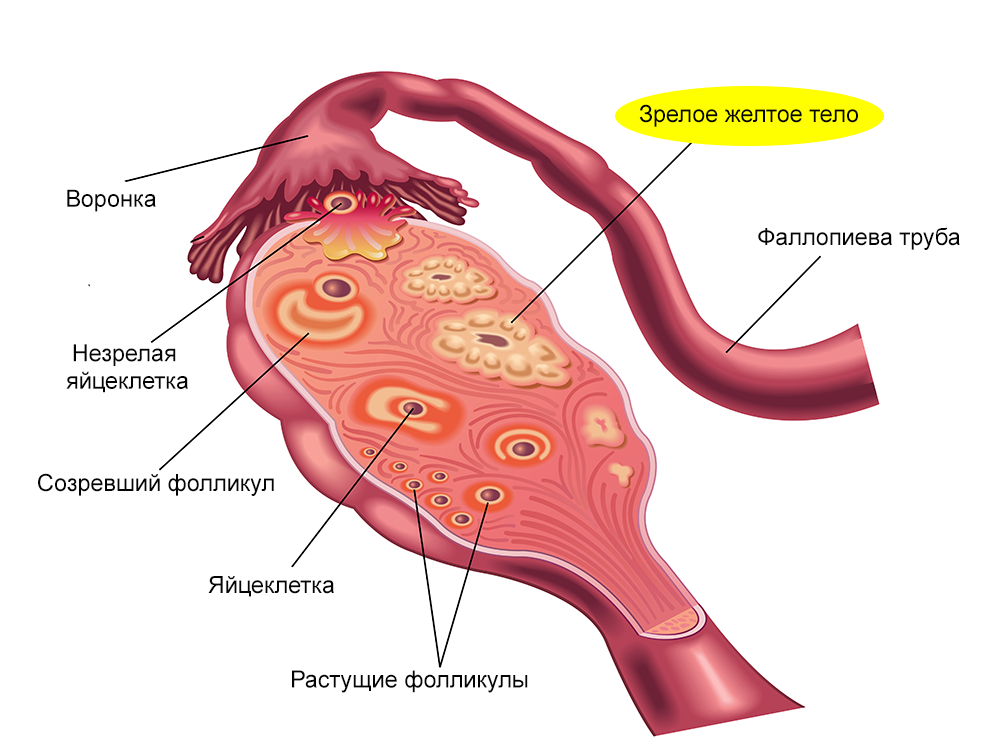

Созревание фолликула в яичнике: этапы и процессы